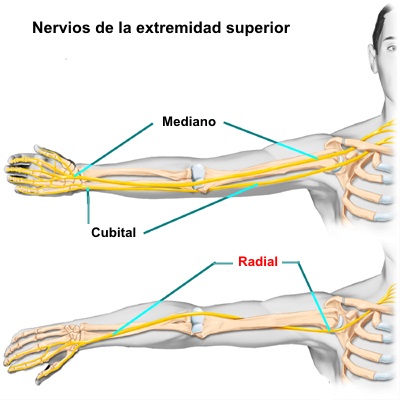

El nervio radial se origina de una rama no

terminal del fascículo posterior del plexo braquial. Pasa por el

brazo, primero en el compartimento posterior del brazo, y luego en

el compartimento anterior del brazo, de donde continúa hasta el

antebrazo y brazo

El nervio radial controla el movimiento del músculo tríceps

ubicado en la parte posterosuperior del brazo. También controla la

capacidad para flexionar la muñeca hacia atrás y ayuda con el

movimiento y la sensibilidad de la muñeca y la mano.